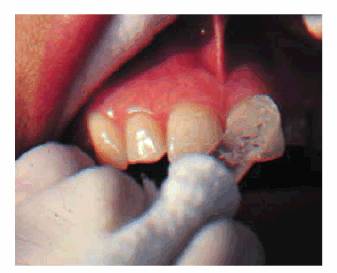

hue would more than likely indicate internal hemorrhage from a recent injury (Figure 19-2), a dental procedure (Figure 19-3), or gingival tissue hyperplasia

Figure 19-3: One week following crown preparation, the tooth structure was red, signifying extravasation of blood and the need for pulp extirpation.

blush on the tooth appears (Figures 19-33A, and 19-33B) during or after preparation, it is

obvious that the 2-mm remaining dentin barrier has been violated. The

probability of complete inflammatory reversibility and healing of a noticeably

hemorrhagic pulp is minimal. Considering that additional procedures are

required to finish the crown, elective endodontics should be instituted before

continuing. If, at any time, a patient elects to forego endodontic therapy

Figure 19-33A: Pink crown preparation 1 week following instrumentation.

Figure 19-33B: Hemorrhagic pulp with extravasation of blood. (Photograph courtesy of Dr. Harold R. Stanley.)